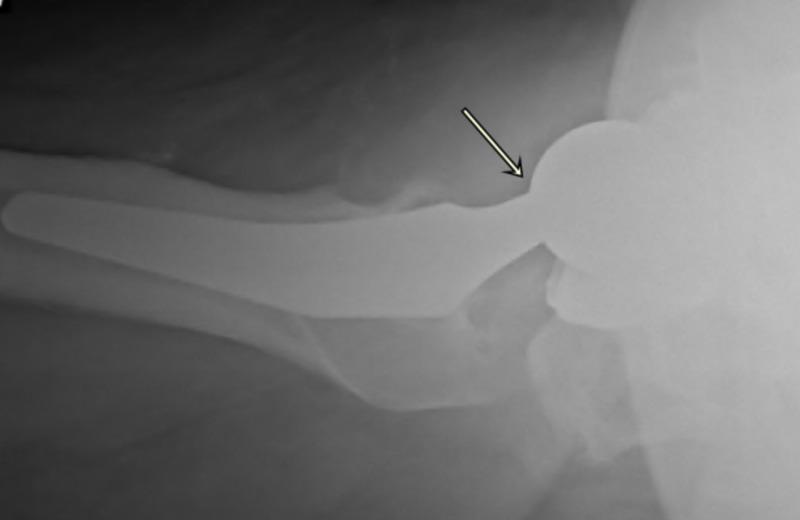

Trunnionosis is a type of corrosion and wear at the head-neck taper junction of the femoral implant, and it can be a slow and silent catastrophe. Simultaneous prosthetic joint infection (PJI) is occasionally possible based on the fulfillment of a few of the minor criteria from the Musculoskeletal Infection Society (MSIS), but the existing literature lacks adequate evidence to support that the infection actually exists. We are presenting a case of an 82-year-old man with right total hip arthroplasty performed over a decade prior to presenting to the emergency room with a sudden-onset pop followed by groin pain and difficulty in walking. Radiographs showed a dissociated femoral implant at the level of trunnion with malalignment and heterotopic ossification. Metal Artifact Reduction Sequence MRI of the right hip showed mixed type-two and type-three pseudotumors, and atrophy of surrounding abductor muscles. The erythrocyte sedimentation rate was within normal limits, C-reactive protein was borderline raised, and serum cobalt-chromium levels were elevated without any signs of systemic metal toxicity. Hip joint aspirate revealed blood-stained fluid flooded with red blood cells, leukocytes and neutrophils, and a positive alpha-defensin assay. These findings were interpreted as positive for prosthetic joint infection. Intraoperatively, there was severe wear of the inferomedial aspect of the femoral head-neck junction and extensive metallosis throughout the right hip. Tissue and fluid specimens were sent for cultures, sensitivities, and histopathology for pseudotumor and infection evaluation. An articulating antibiotic spacer was then placed with the intent to perform a staged reconstruction of the femur and right acetabulum. Final synovial, bone, and soft tissue cultures, as well as histopathological photomicrograph of the tissue slides, were negative for infection. This case demonstrates the striking features of metallosis associated with trunnion failure of a metal-on-polyethylene total hip joint prosthesis that was simultaneously showing signs of prosthetic infection by satisfying the minor criteria according to the latest guidelines by the MSIS with a strikingly high cell count of red blood cells in the synovial fluid exam, indicating inflamed hyper-vascular pseudotumors vs. hemarthrosis vs. bloody tap. Diagnostic dilemma led by positive synovial fluid alpha defensin, high synovial neutrophil and white cell count results with negative final cultures or infection on histological slides raises concern that infection was not present and two-stage revision arthroplasty with six weeks of antibiotics was not necessary along with increased risk of morbidity, mortality as well as cost of care.

股骨柄腐蚀是指股骨植入物头颈锥度交界处的一种腐蚀和磨损情况,它可能是一场缓慢且悄无声息的灾难。根据肌肉骨骼感染学会(MSIS)的一些次要标准,偶尔可能会同时发生人工关节感染(PJI),但现有文献缺乏足够证据支持感染实际存在。我们报告一例82岁男性患者,该患者在十多年前接受了右全髋关节置换术,之后因突然出现的砰的一声响,随后出现腹股沟疼痛和行走困难而前往急诊室就诊。X线片显示股骨柄水平处股骨植入物分离,伴有排列不齐和异位骨化。右髋关节的金属伪影减少序列MRI显示为混合型二型和三型假肿瘤,以及周围外展肌萎缩。红细胞沉降率在正常范围内,C反应蛋白略升高,血清钴铬水平升高,但无任何全身金属中毒迹象。髋关节穿刺抽出的液体为血性,充满红细胞、白细胞和中性粒细胞,α-防御素检测呈阳性。这些结果被解释为人工关节感染呈阳性。术中发现股骨头颈交界处的内下侧严重磨损,整个右髋关节有广泛的金属沉着症。将组织和液体标本送去进行培养、药敏试验以及用于假肿瘤和感染评估的组织病理学检查。然后放置了一个可活动的抗生素间隔物,打算分阶段重建股骨和右髋臼。最终的滑膜、骨和软组织培养结果,以及组织切片的组织病理学显微照片显示感染为阴性。该病例展示了与金属对聚乙烯全髋关节假体股骨柄失效相关的金属沉着症的显著特征,根据MSIS的最新指南,该病例同时通过满足次要标准显示出人工感染的迹象,在滑膜液检查中红细胞计数极高,提示为炎症性高血管假肿瘤与关节积血与血性穿刺的区别。滑膜液α-防御素阳性、滑膜中性粒细胞和白细胞计数高且最终培养结果或组织学切片感染为阴性所导致的诊断困境,引发了人们对感染是否存在的担忧,以及六周抗生素治疗的两阶段翻修关节成形术是否必要,同时还增加了发病、死亡风险以及护理成本。